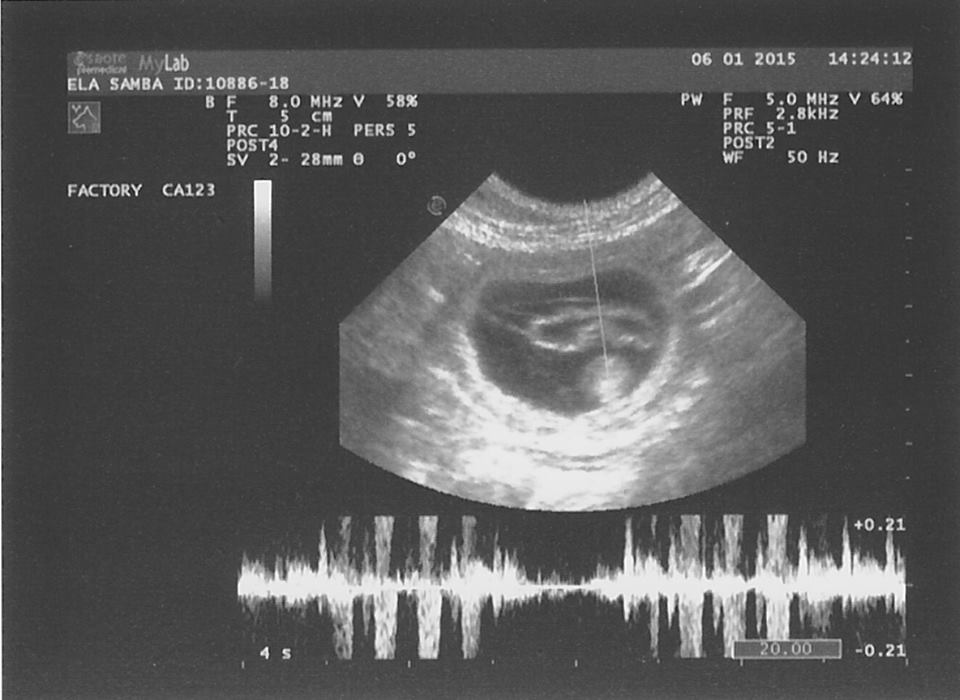

De echo voorspelde geen groot nest maar zo is maar weer bewezen dat een echo niet altijd nauwkeurig is. Deze verassing is natuurlijk alleen maar leuk, meer pupjes is altijd goed.

Ela is drachtig!